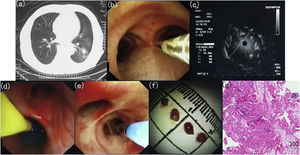

Fig. 1 illustrates the details of r-EBUS guided TBLC. Prior to the procedure, a solitary pulmonary nodule with a positive CT bronchus sign in the left lower lobe was determined on the CT scan. Following moderate-to-deep conscious sedation with intravenous midazolam and fentanyl, a 20-MHz r-EBUS probe with an external diameter of 1.4 mm (UM-S20-17S; Olympus, Tokyo, Japan) was extended into the lung periphery through the working channel of the bronchoscope. r-EBUS imaging showing a concentric lesion (i.e., the r-EBUS probe was within and completely surrounded by the lesion) with no significant surrounding vessels. An endobronchial blocker was then placed at the target segmental bronchi. Subsequently, cryobiopsy was performed (ERBE Cryoprobe 1.9 mm diameter, Medizintechnik, Tuebingen, Germany) with the foot pedal switch of Cryostation being activated for 5 s. The cryoprobe was quickly retracted en bloc together with the flexible bronchoscope from the patient. Upon removal of the cryoprobe, the pre-placed endobronchial blocker was inflated with air immediately in order to control bleeding after procedure. All biopsy specimens were fixed in formalin and sent to the pathology lab immediately for further analysis. Immunohistochemical and molecular analysis revealed lung adenocarcinoma with sensitizing epidermal growth factor receptor (EGFR) mutation.

Details of transbronchial lung cryobiopsy (TBLC) guided by radial endobronchial ultrasound (r-EBUS).(a) Computed tomography (CT) scan of the chest showing a solitary pulmonary nodule located in the left lower lobe; (b) The placement of the r-EBUS probe into the target bronchus; (c) r-EBUS imaging showing a concentric lesion with no significant surrounding vessels; (d) An endobronchial blocker is placed in the proximal lobar bronchus from the lesion and is inflated after procedure; (e) The placement of the cryo-probe into the target bronchus; (f) Bioptic specimens with sizing scale collected through TBLC; (g) Immunohistochemical analysis revealing lung adenocarcinoma.